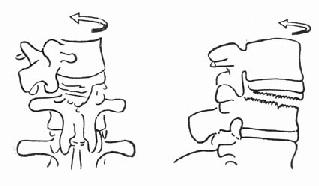

(四)剪力骨折 又称切片状骨折(slice fracture)。常为屈曲旋转暴力引起,脊椎前、后方所有韧带均撕裂,可伴有一侧或两侧小关节、横突及椎弓根的骨折,但椎体骨质破坏不明显,椎体高度不变。但旋转剪力可将下一个椎体上缘撕脱小片骨质,就像刀切下一薄片一样(图73-5)。由于所有结构几乎完全横断,骨折高度不稳定,病人常常合并完全截瘫。X线片可见“切片”状骨折片和椎间隙增宽的特点。

(五)椎体后部骨折 又称座带骨折(seat belt fracture)。由Chance于1948年首先描述此骨折,故文献又常称Chance骨折,为一种屈曲拉伸骨折。典型的损伤机制为汽车座带束于患者腰腹部,当高速行驶的汽车突然减速或撞车时,座带支点以上的躯干屈曲,前冲力还同时产生一个向前拉伸的力量(图73-6)。将椎体由后方向前撕裂,骨折线横过椎体、椎弓根和椎板,椎体后部的韧带完全撕裂(图73-7)。有时前纵韧带亦可撕裂,常合并有神经系统的症状。

图73-5 旋转剪力作用

图73-6 座带骨折机制

图73-7 座带骨折的骨折线

(六)拉伸骨折 又分两种,屈曲拉伸损伤(图73-8),Chance骨折亦属此型。过伸拉伸损伤,前纵韧带撕裂,椎体上端略向椎管处移位(图73-9),常为汽车从后方撞于腰部引起。

图73-8 屈曲拉伸损伤

图73-9 过伸拉伸损伤